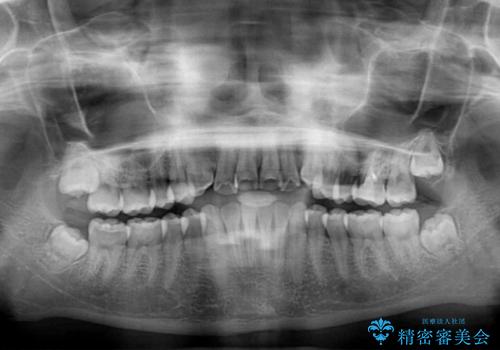

- 海外留学の予定があるが、学生のうちに歯列を整えたいとのことで来院された患者様です。

前歯にデコボコがあり、口元がやや突出した印象があったため、IPR(歯と歯の間を削る)と親知らずを抜歯した上での歯列全体の後方移動をメインに、インビザラインを用いて矯正治療を行うこととしました。